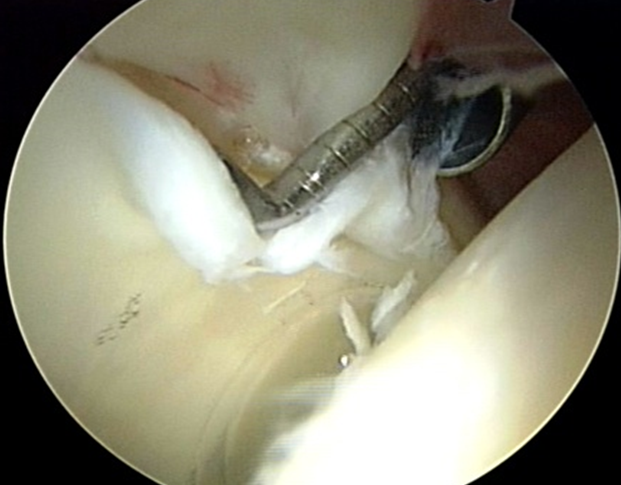

Raggiunta l'articolazione dell'anca si esegue una valutazione in toto dello spazio e delle superfici articolari per verificare l'esatta entità del danno osteocartilagineo, spesso sottostimato dalla valutazione strumentale pre-operatoria e poi si procede all'intervento chirurgico vero e proprio. Per la valutazione e il trattamento della regione periferica (collo del femore) si lavora senza trazione e l'anca viene flessa e ruotata (flessione 45 gradi, rotazione 30 gradi). Diversi strumenti artroscopici potranno essere introdotti nell'articolazione in relazione alle diverse procedure da effettuare (fig. 10).

Al termine della procedura chirurgica possono essere eseguite infiltrazioni intra articolari con farmaci antinfiammatori e anestetici locali per ridurre al minimo il dolore nel post-operatorio. Le vie di accesso artroscopiche vengono suturate con 1-2 punti ognuna e medicate.